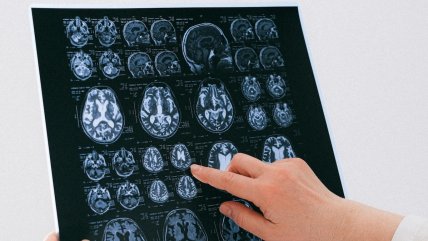

Las cinco etapas del cerebro humano: estudio revela cambios clave a los 9, 32, 66 y 83 años